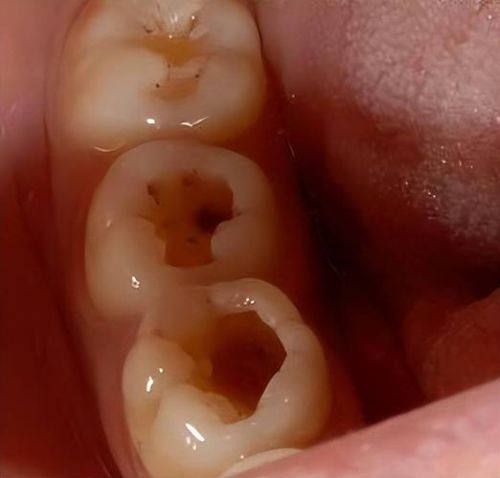

蛀牙,也就是龋齿,是一种常见的口腔疾病。它主要是由于口腔内的细菌利用食物残渣中的糖分产生酸性物质,这些酸性物质会逐渐腐蚀牙齿的硬组织,导致牙齿表面出现龋洞。如果不及时处理,龋洞会越来越深,更终可能会影响到牙髓,引起剧烈疼痛。了解蛀牙腐蚀的过程和危害,对于我们采取有效的措施让蛀牙停止腐蚀至关重要。

当龋坏发展加重到一定程度,造成局部明显牙体组织缺损时,就需要进行修复性治疗了。医生会先去除牙齿表面的龋坏部分和无基釉,然后修整制备洞型。接着选择合适的牙科材料逐层进行修补,这样可以修复牙齿的形态和咬合功能。修复性治疗能够完全去除龋坏组织,防止蛀牙继续腐蚀,让牙齿修复健康。